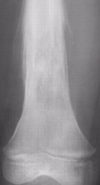

Los extremos del hueso aparecen ensanchados (en pata de elefante) En este caso el principal problema es la falta de estabilidad. El hueso tiene capacidad para consolidar, pero los micromovimientos en el foco impiden que la consolidación se complete. Requieren síntesis rígidas a compresión como tratatamiento de elección (enclavado intramedular